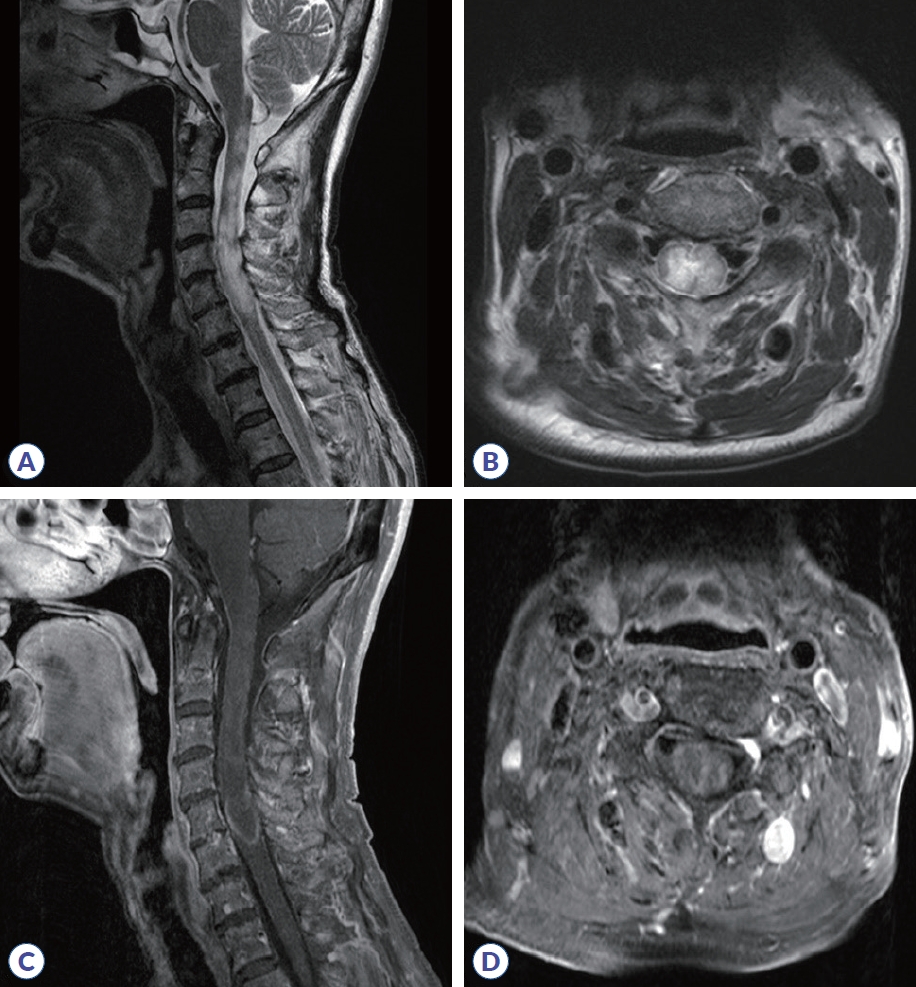

Aquaporin-4 Antibody-Positive Neuromyelitis Optica Spectrum Disorder Triggered by Herpes Zoster: A Case Report and Literature Review

Daecheol Moon, Dong Kyu Kim, Seong-il Oh

J Mult Scler Neuroimmunol. 2025;16(2):60-65.

Case Report

Dec 31, 2025